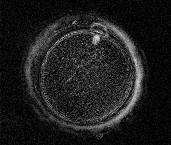

上下同じ卵子で、下段の写真は普通の顕微鏡で観察した卵子、上段の写真は偏光を試用した特殊な顕微鏡(Polscope)で観察した卵子。

精子を振りかけた3時間後の受精前の卵子

極体が1個見え、上側の写真は極体の下に白い紡錘体が見える。

精子を振りかけた6時間後の受精進行中の卵子

精子が卵の中に入り受精進行中の卵子で、紡錘体が消失し極体が2個ある。

受精する前の成熟した卵子は、極体が1個あり、極体の下に紡錘体(染色体)があります。精子が卵子の中に入り受精が進行すると、卵子の中から2個目の極体が出て紡錘体は消失します。極体と紡錘体の状態で精子が入り受精が進行しているかを判断します。

極体が2個あるように見えていても、1個の極体が2個に割れているだけで受精していない卵子もあり、紡錘体を観察することで受精が進行しているかが判ります。精子が入っている卵子に、受精が進行していないと判定し、ICSIを行うと異常な受精卵になり、精子が入っていない卵子に受精が進行していると判定すると受精せず、受精進行の正確な判定が重要で、紡錘体の観察が役立ちます。